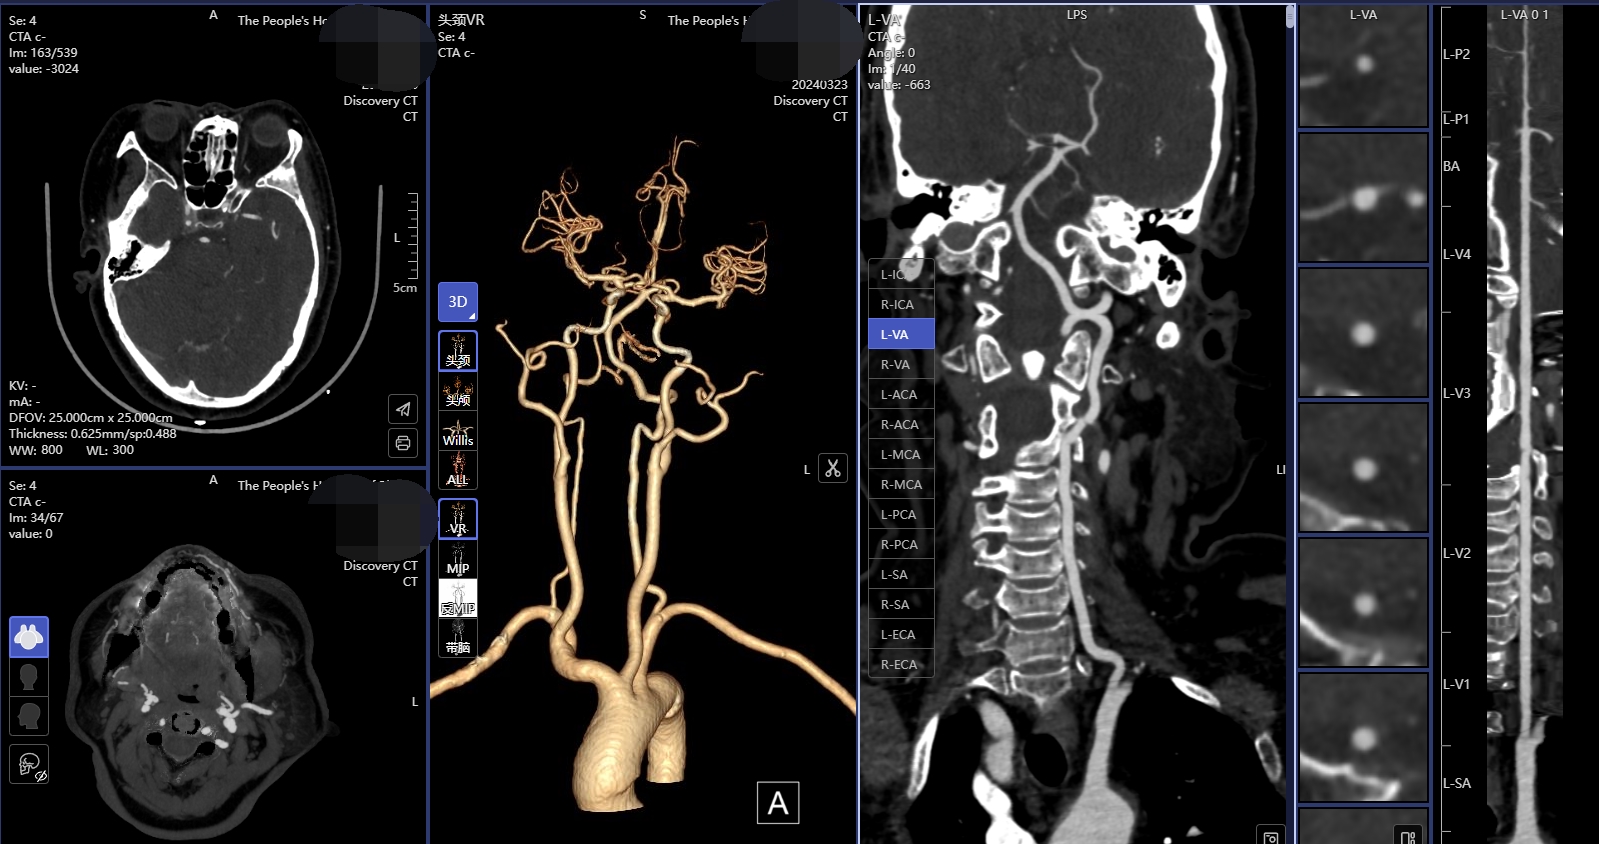

【技術一】腦卒中“一站式”CT檢查,包括CT平掃(NCCT),CT血管成像(CTA)和CT灌注成像(CTP),成像方法簡便,3-5分鐘即可完成檢查。只需一次檢查即可完成腦卒中治療前評估,為患者得到及時有效的治療提供有力支持。

【腦卒中“一站式”CT檢查】